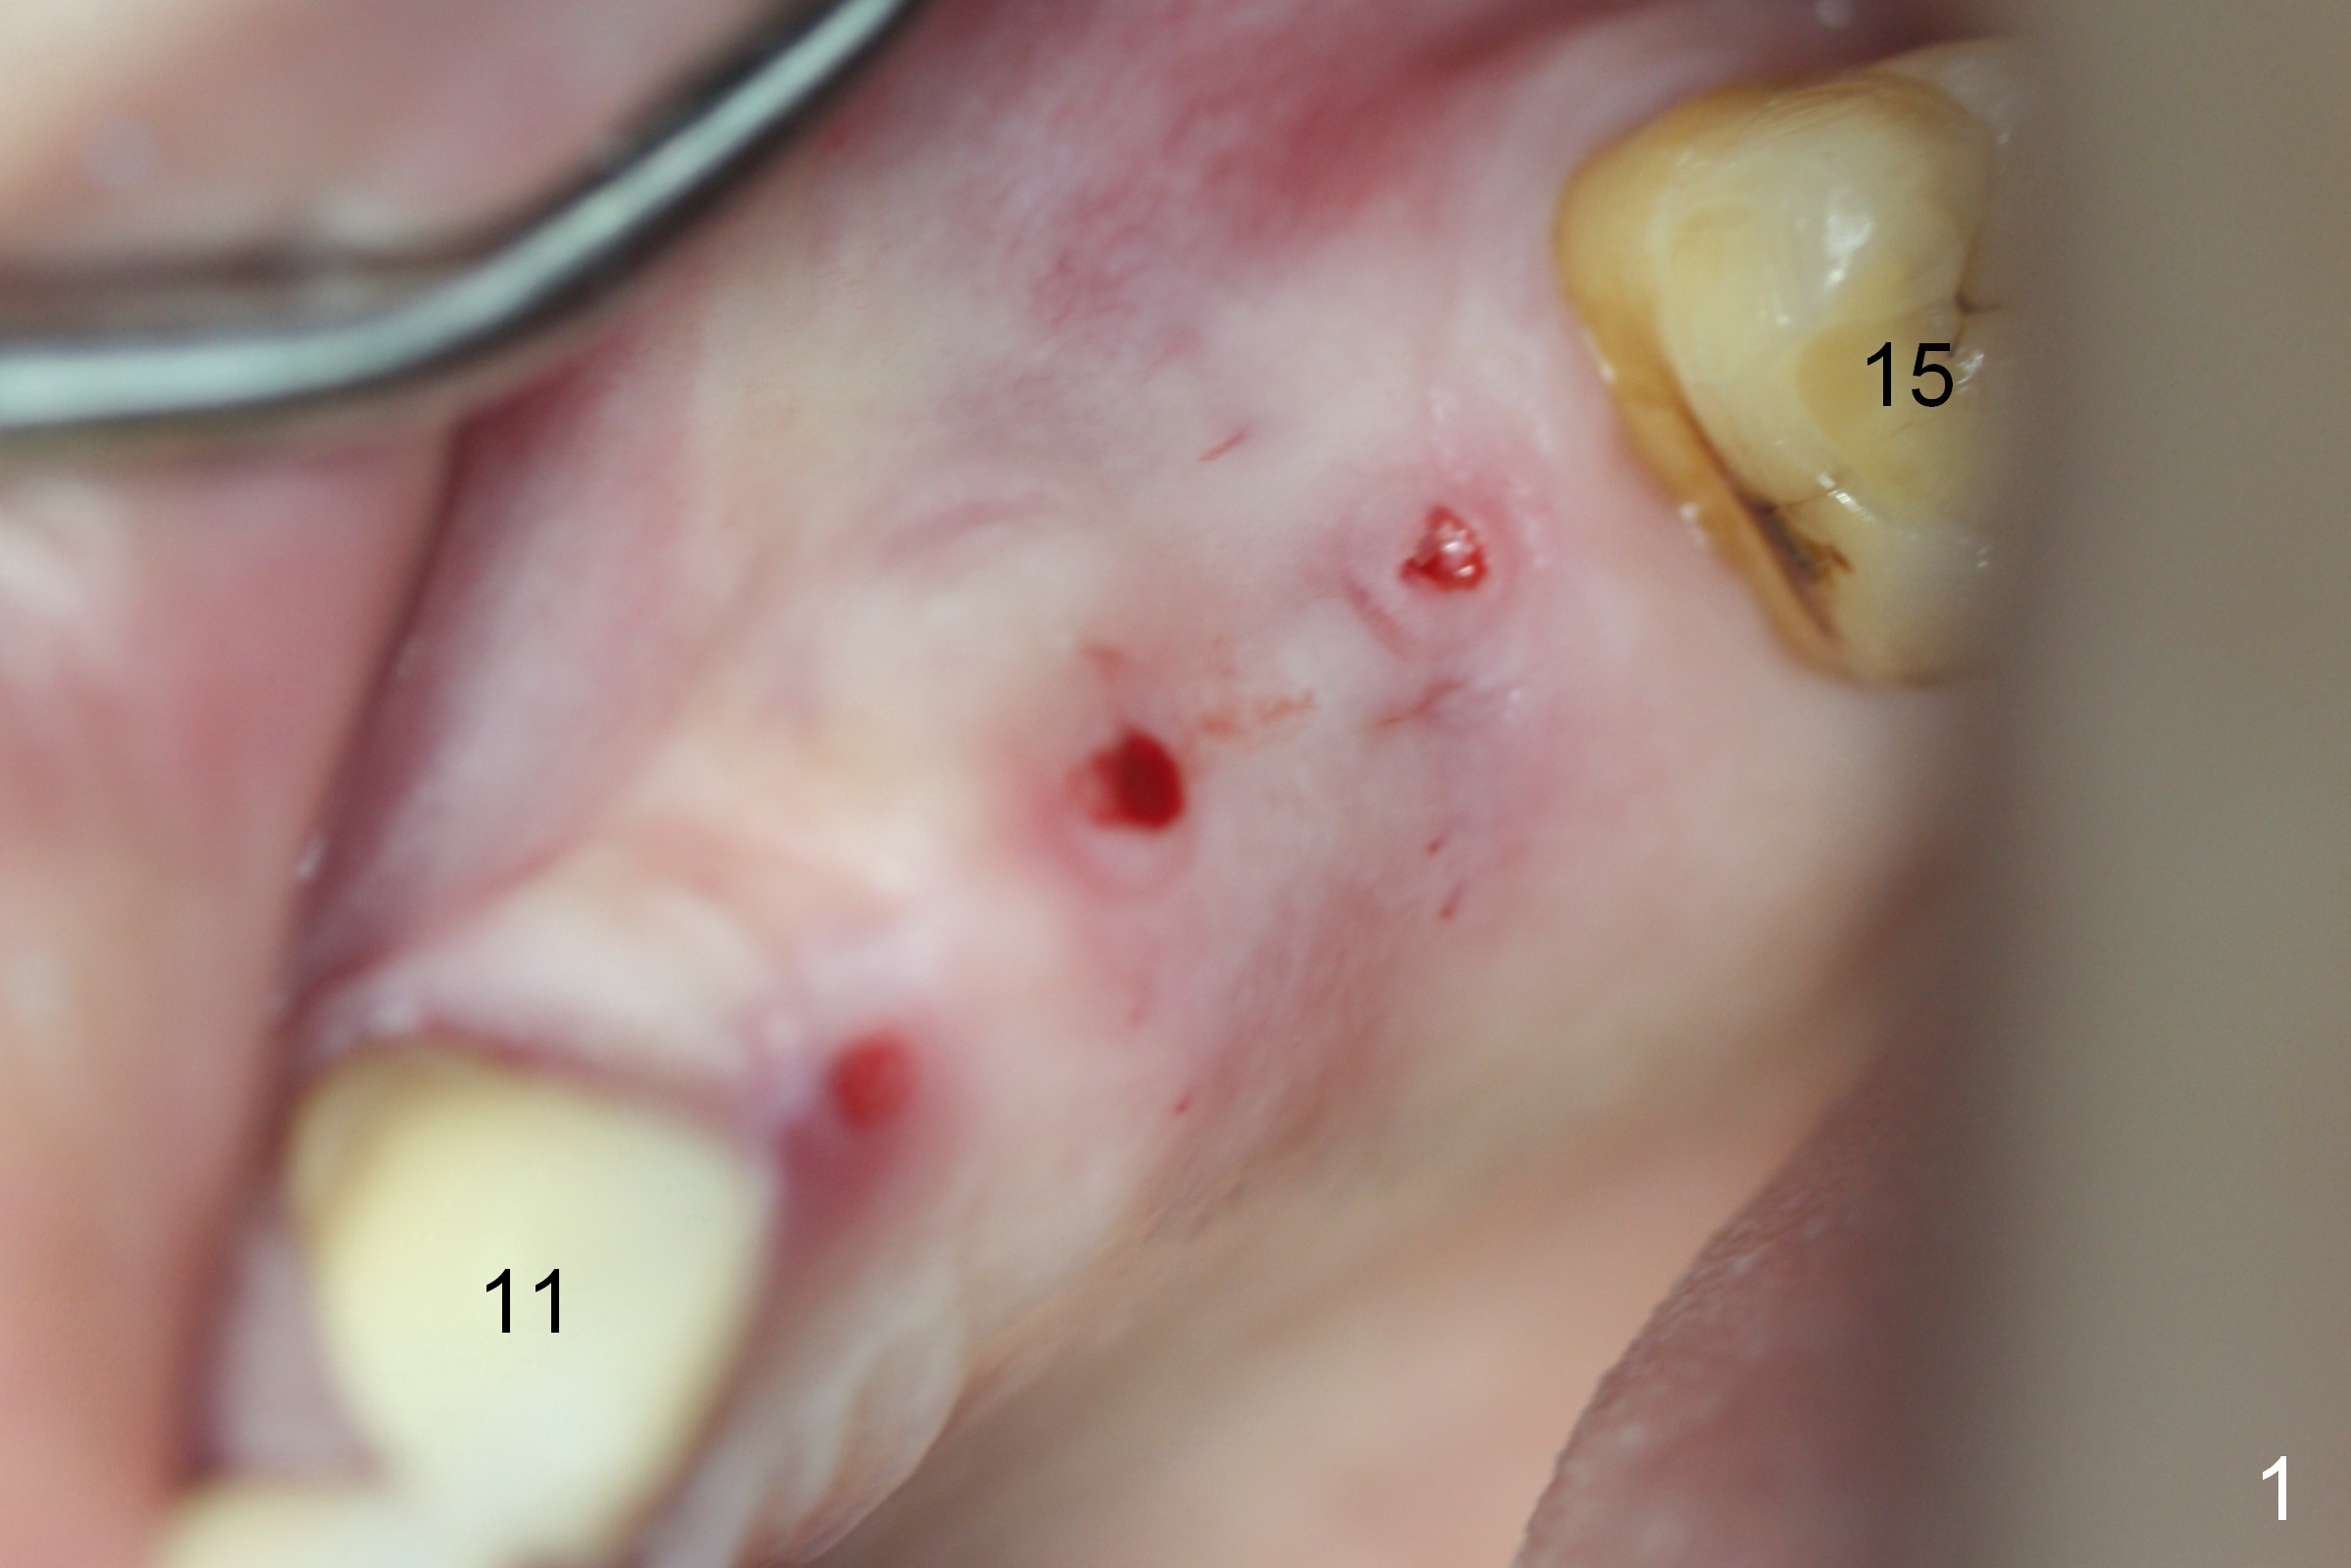

Initial osteotomies are established at the sites of #12-14 through the surgical guide (Fig.1). Following incision, the position of the osteotomies is adjusted buccopalatally where needed. Initial depth is 10 mm (Fig.2); final 14 mm. Ridge split is accomplished between the osteotomies with 7,10 and 13 mm saws from Esset Kit (Hiossen). The osteotomies are enlarged by bone expander drills from the Esset Kit RPM (Fig.3 D). When implants are placed (Fig.4 I (4.1, 3.8 and 5x14 mm)), the gap of split ridge does increase and is subsequently closed by bone graft and membrane. Definitive abutments (A) are installed to hold periodontal dressing in place securely. CBCT study reveals that the bone density between #12-14 are <200 Hounsfield units. When HU is >400, ridge split may result in bone fracture.